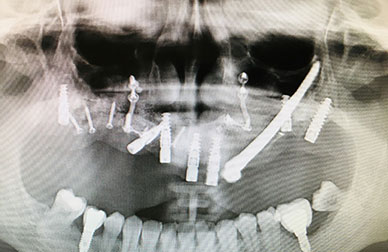

Implantes sobre maxilar muy deteriorado

Implantología avanzada